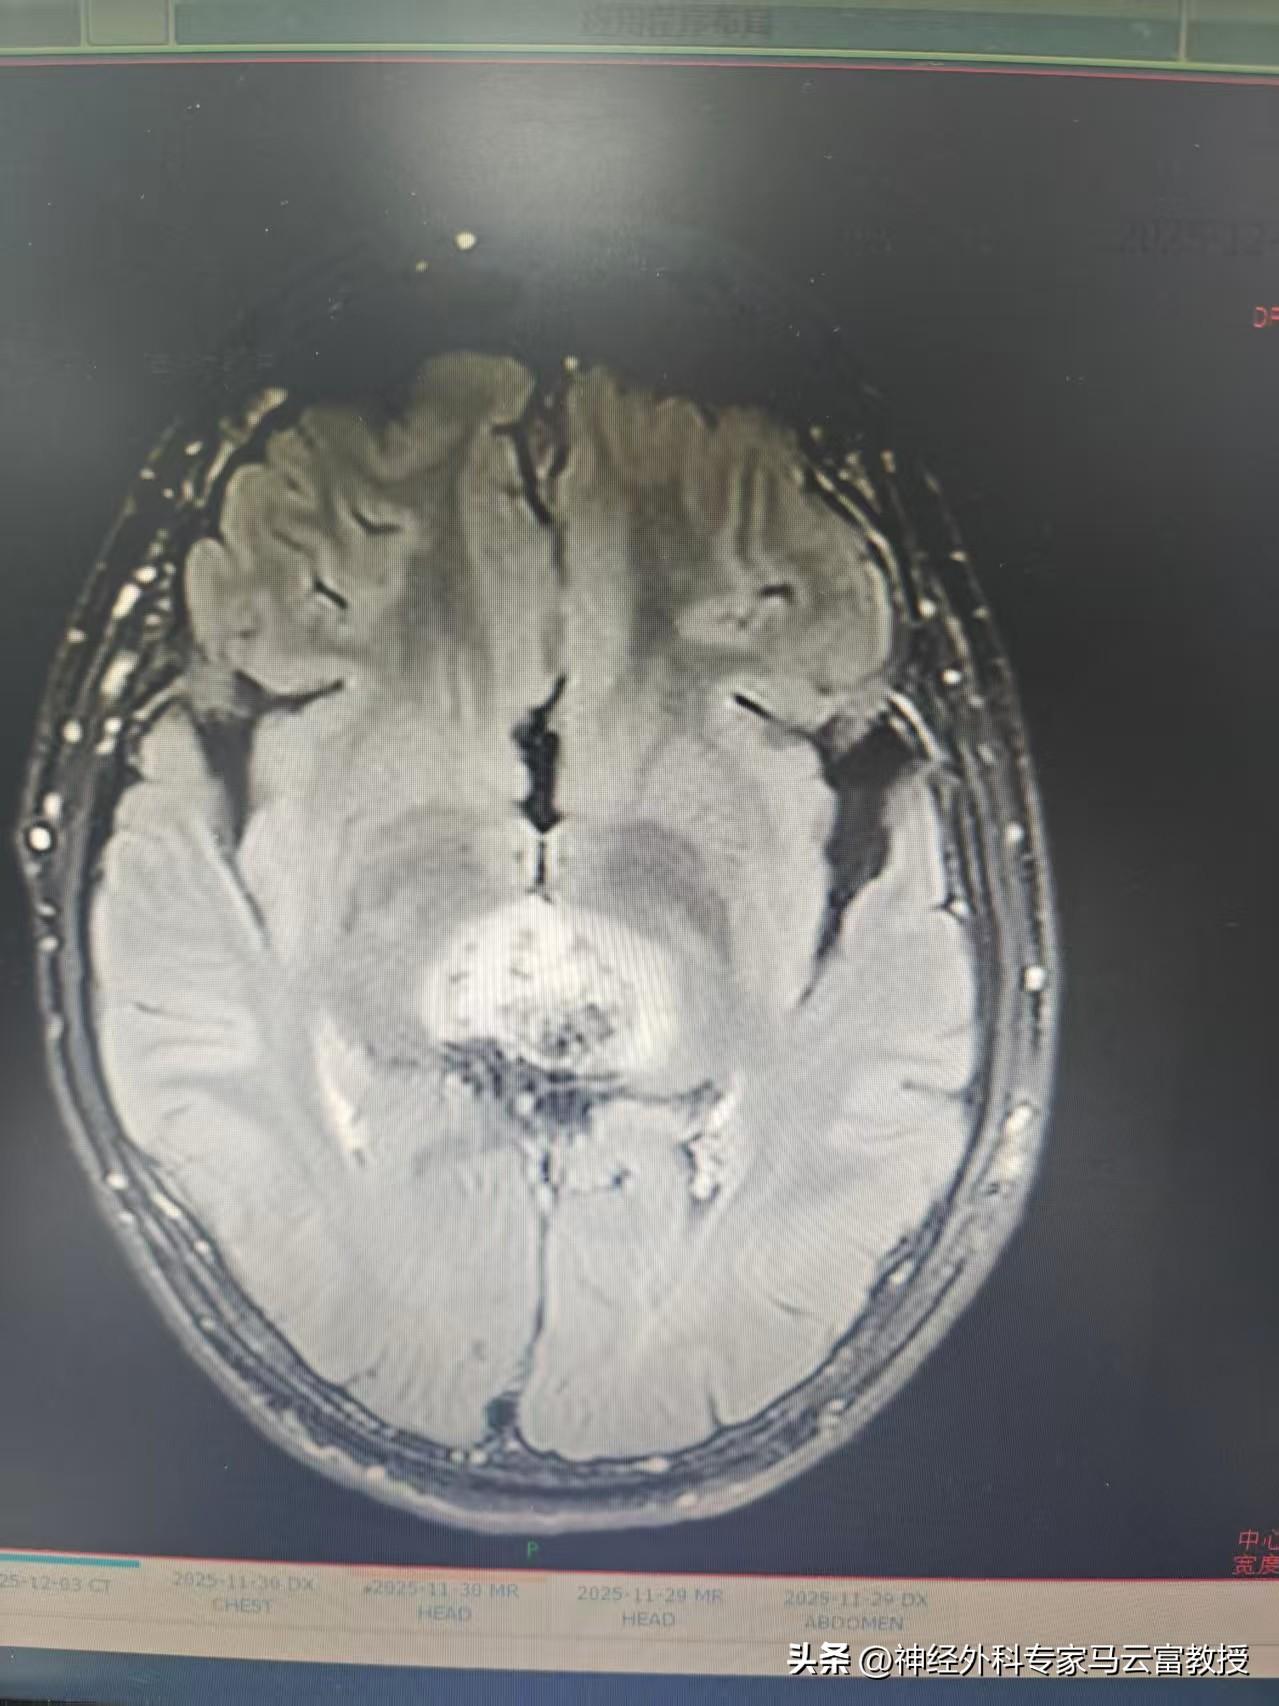

目前,小明已成功完成第一階段化療,期間未出現明顯噁心嘔吐,血常規監測亦未出現白細胞、血小板顯著下降等不良反應,身體耐受良好。近期複查頭顱MRI顯示,顱內佔位病變範圍較前有所縮小,病情初見控制成效。

第一階段化療後腦MRI